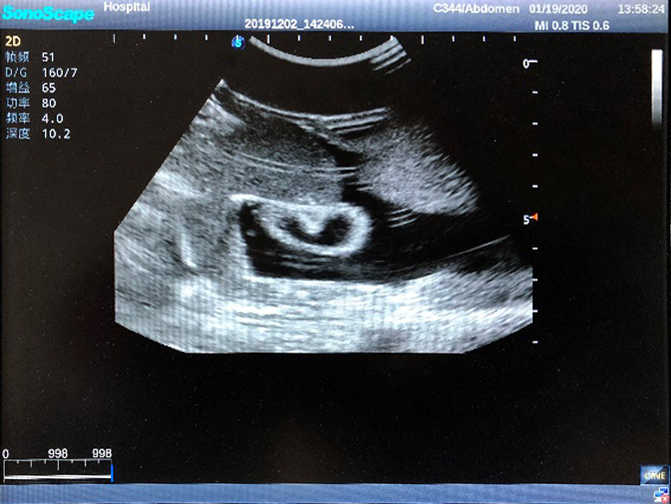

2)  High quality ultrasound image with clear structures like gallbladder, liver, intestines, arteries and veins etc.

4)  ltrasound gallbladder pathologies like cholecystitis, gallstone and polypoid degeneration

5)  Normal & pathological ultrasound live and intestine models inside